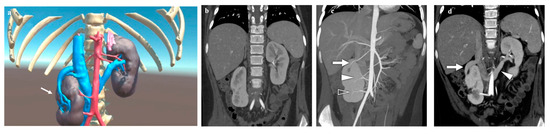

3.2. Adrenal Lesions

| Case n. 2 | Male | 7 years | Adrenal myelolipoma | Right |

| Case n. 3 | Male | 9 years | Ganglioneuroblastoma | Right |